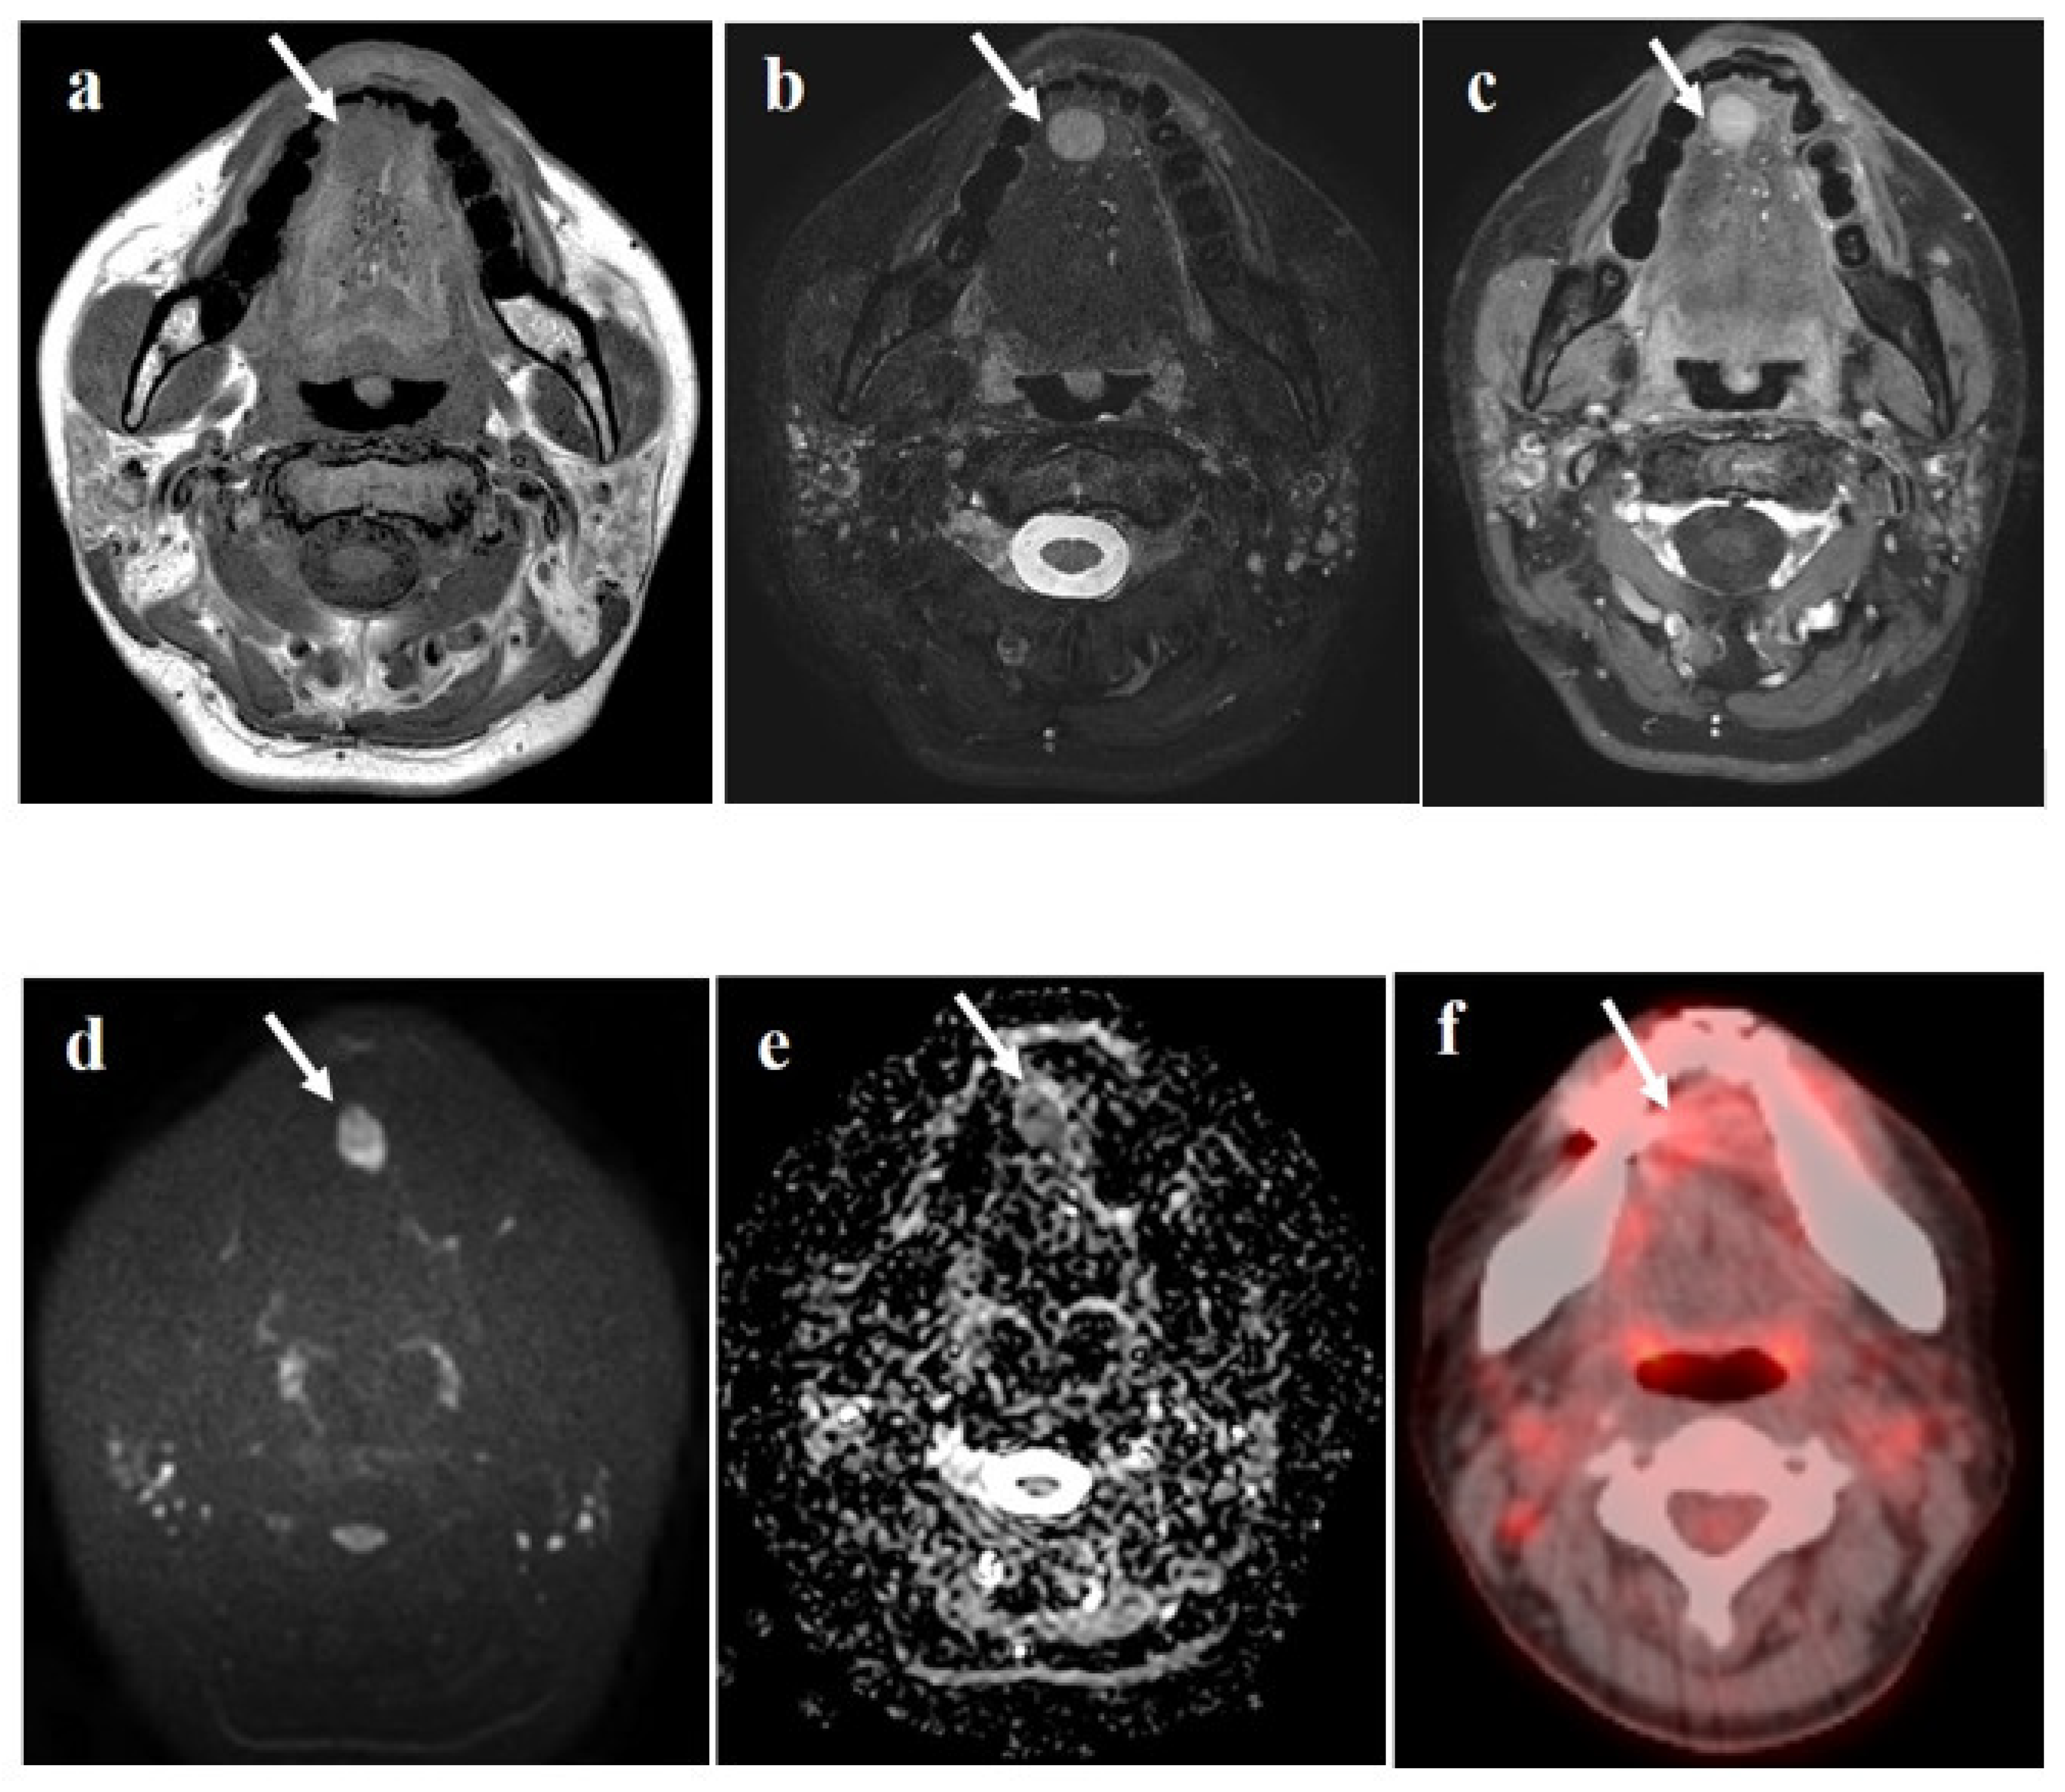

2. Case Report